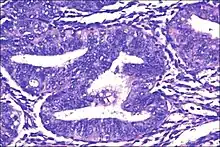

| Micrograph showing simple endometrial hyperplasia, where the gland-to-stroma ratio is preserved but the glands have an irregular shape and/or are dilated. Endometrial biopsy. H&E stain. | |

Endometrial hyperplasia is a condition of excessive proliferation of irregular size and shaped endometrial glands in the uterus, without significant cytoplasmic atypia.[1]